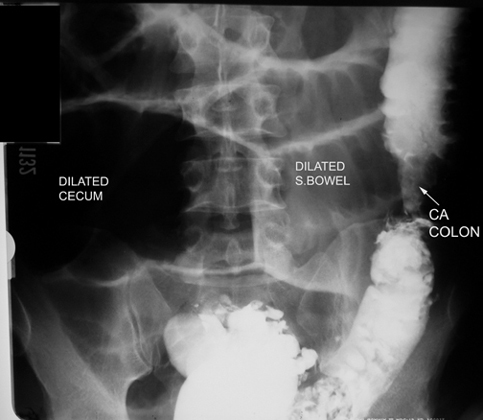

Large bowel Obstruction

• Dilated bowel loops proximal to the obstruction.

• Arrow points to the etiology of obstruction.